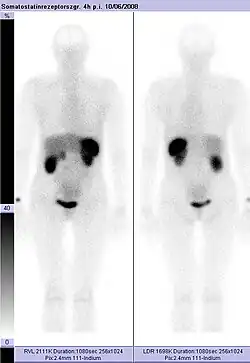

Somatostatin-Rezeptor-Szintigrafie

Normale Aktivität in Leber, Galle, Milz, Nieren und Harnblase

Unmittelbar vor der Injektion wird das Konjugat Komplexbildner–Somatostatin-Analogon mit dem Radioisotop, meist 111Indium, beladen. Die freien Indiumionen werden durch den Komplexbildner vollständig chelatisiert. Das so hergestellte Radiopharmakon wird intravenös appliziert und verteilt sich dabei im Blutkreislauf des Patienten. An Zellen, die entsprechende Somatostatin-Rezeptoren besitzen, reichert sich das Radiopharmakon an. Dies sind unter anderem der Hypothalamus, die Großhirnrinde und der Hirnstamm, sowie eine Reihe von Tumoren und deren Metastasen. Etwa vier Stunden nach der Verabreichung des Radiopharmakons wird eine erste Aufnahme durchgeführt. Die Dauer beträgt etwa eine Stunde. Das angereicherte Radiopharmakon zerfällt. Die dabei abgestrahlte Gammastrahlung durchdringt das umgebende Gewebe und wird mittels einer Gammakamera detektiert und per Bildverarbeitung zu einem Bild zusammengesetzt. Die Anzahl der Zerfallsereignisse ist in den Bereichen der Anreicherung besonders hoch. Am nächsten Tag wird meist eine zweite Szintigrafie durchgeführt (siehe auch: Szintigrafie und Single Photon Emission Computed Tomography).